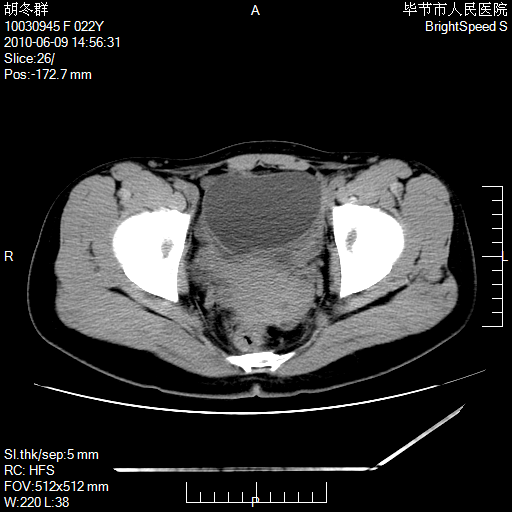

患者23岁,发现腹部包块3月。

左侧卵巢囊腺瘤或囊腺癌

盆腔内囊性占位性病变;考虑左侧卵巢囊腺瘤。

有分隔、壁薄,支持考虑左侧卵巢囊腺瘤。

左侧卵巢浆液性囊腺瘤。

支持考虑左侧卵巢囊腺瘤;宫腔积液。

有分隔、壁薄,支持考虑左侧卵巢囊腺瘤。排尿后,膀胱缩小,由于重力作用,肿块下移就到了膀胱位置,很好理解。